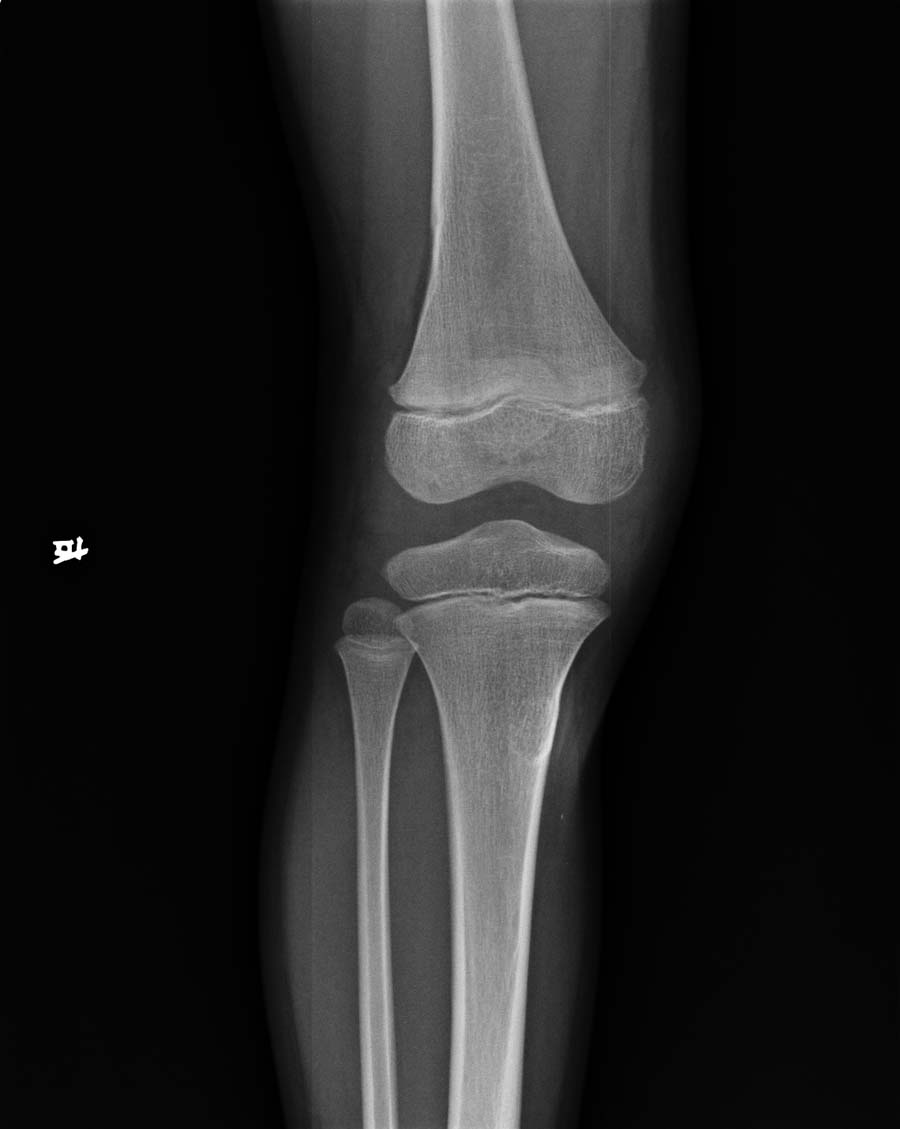

以下是引用杀毒软件在2008-5-26 22:37:00的发言:[br]右胫骨纤维性骨皮质缺损可能性大

以下是引用蚂蚁在2008-5-26 23:01:00的发言:[br]宽基底骨软骨瘤!